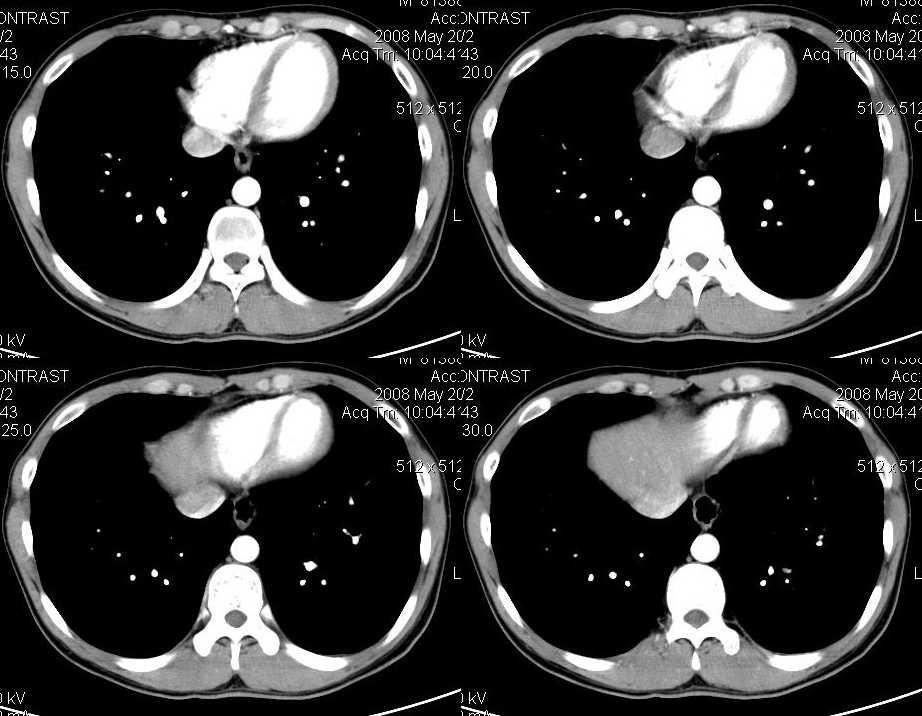

以下是引用liuyue在2008-6-7 15:28:00的发言:[br]典型的:肾癌。[br]动脉期强化明显,而静脉期密度明显降低,呈低密度。